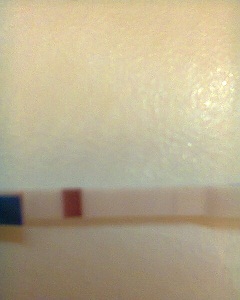

Slabý duch na teste

Ahojte zienky.. prosim vas o radu.. neviem ci to vidim len ja, alebo su tam naozaj dve ciarky??? 😒 ja tam vidim slabulilinkeho ducha na kazdom teste.. dnes som 27dc, mavam pravidelne 25dnovy cyklus, takze uz treti den mi meska mrcha.. uz dva tyzdne mi byva obcas trosku nevolno (ale zas neviem ci si to len namyslam alebo je to tak) prosim poradte mi, to cakanie ma ubija.. o dietatko sa snazime druhy mesiac, jedno dvojrocne uz mame 🙂

- Slabé ružové čiarky na domácich tehotenských testoch často predstavujú "ducha" alebo presvitajúce sfarbenie a nie vždy znamenajú ochytenie; odporúča sa opakovať test po vynechaní menštruácie alebo potvrdiť krvnými testami u lekára.

A: Diskusia uvádzala, že ide môže ísť o "ducha" alebo čiarku, ktorá po vyschnutí zmizne (tzv. evaporation line); odporúčaný postup je urobiť opakovaný test o pár dní alebo dať odobrať krv na hCG u lekára.

@barboritta ahoj prosim ta pozri moje mam v snazilkach aj vo fore duch na teste je to tiez kanlik foto je troska upravena budem rada ak odpises

@turbakova mne sa zdá,že na tom teste pod tým žltým niečo vidím,aj na poslednom trošičku,ale skôr mi to príde ako premočený test.ja som takto duchovala pred pár dňami a dostala som,dokonca som mala čiaarky výraznejšie ako ty.podľa mňa ked tehotná budeš,žiadnycg duchov hľadať nebudeš,ale bude to jasné.nevešaj hlávku,možno o mesiac.ale možno sa aj mýlim.daj vedieť